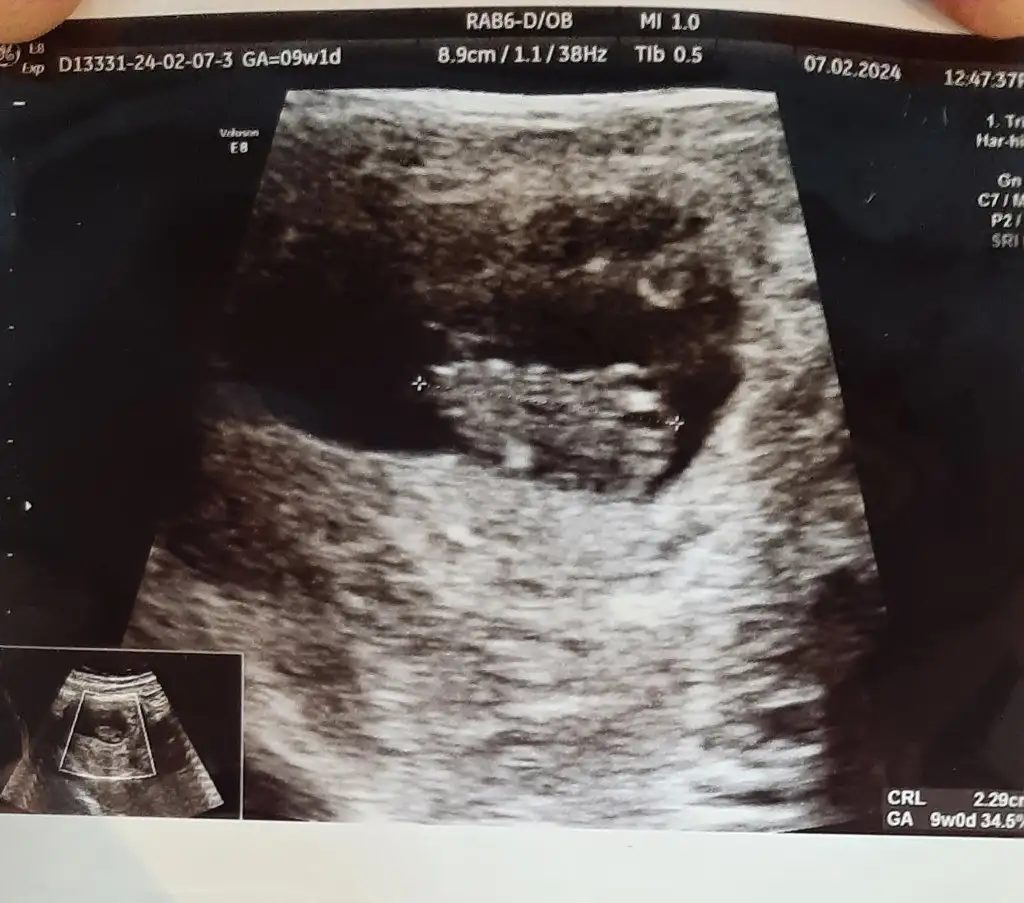

Valla onları demedi neden demedi bilmiyorum kendi baktı herşey yolunda dedi cinsiyetide söylemiyordu ben sordum kıza benziyor ama bu haftalarda yanılma olur değişebilir bidaki gelmene netleşir dedi bakalımYaaa ben onu yerim ne kadar net maşallah canım kaç cm ve kaç gram dedi doktor

Ultrason kağıdında boyu ve kilosu yazıyor kuzum bakabilirsin doktorunuzun söylemesine gerek yokValla onları demedi neden demedi bilmiyorum kendi baktı herşey yolunda dedi cinsiyetide söylemiyordu ben sordum kıza benziyor ama bu haftalarda yanılma olur değişebilir bidaki gelmene netleşir dedi bakalım

Normalde söylüyordu o yüzden dedim sağol canım bakarım ben atmıştım burayada ultrason fotosunuUltrason kağıdında boyu ve kilosu yazıyor kuzum bakabilirsin doktorunuzun söylemesine gerek yok